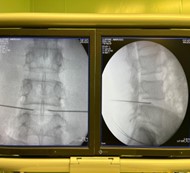

• Autore di vari articoli in "Tecniche e Procedure mini-invasive in Terapia del Dolore" particolarmente nel trattamento dell'ernia discale;

• Attualmente 550 interventi di "Decompressione Percutanea del Ernia Discale" da primo operatore;

Foto e Video